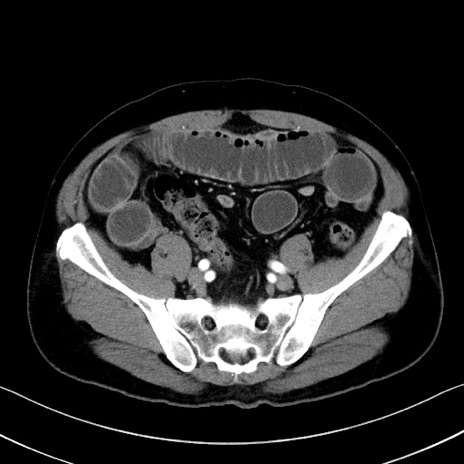

症例35(横断像)

【症例】70歳代 男性

【主訴】腹部膨満、嘔吐

【現病歴】昨日より腹部膨満感出現。本日増悪し、仙痛出現。嘔吐あり、受診。

【既往歴】糖尿病、胆摘後

【身体所見】BP 149/80mmHg、HR 74/min、BT 35.9℃、腹部:膨満、軟、圧痛なし。腸雑音減弱あり。上腹部正中切開瘢痕あり。

【データ】WBC 13500、CRP 1.72